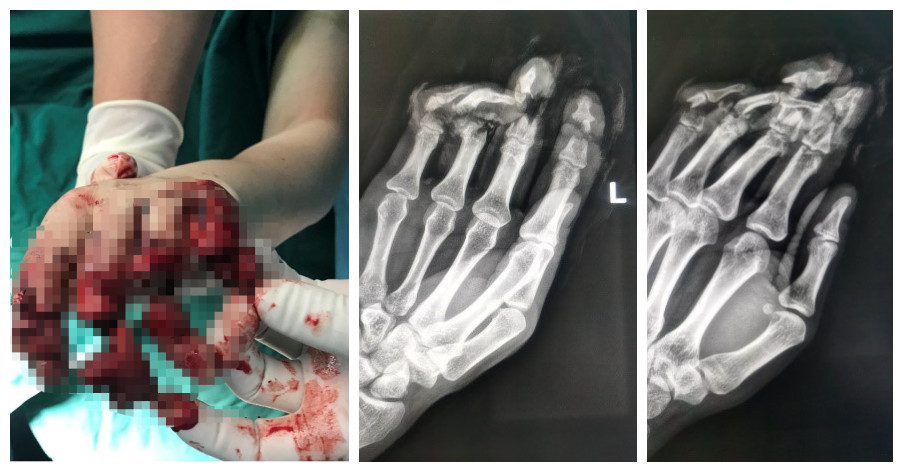

不久前,赵先生工作时被电锯不慎锯伤,随后被紧急送往厦大翔安医院。骨科医生检查创口见:左手第2-5指离断,创缘软组织捻挫严重,示指仅腹侧少量皮肤相连,中指、小指仅一细细皮条相连,环指仅残存部分屈肌腱相连,指端色白、皮温低,压之萎陷、无弹性。X线示:左手2-5指中节指骨粉碎性骨折,骨折断端不规则,可见多个游离骨碎片。

骨科周大果主任医师分析:患者为电锯伤致四指离断,断端软组织碾、创面污染严重,且骨质、神经、血管、肌腱部分缺失,再植条件不好,手术难度较高、成活率较低。

对于周大果主任医师来讲,断指再植手术已经轻车熟路,骨性结构、血管、神经、肌腱一一有条不紊地被重建,经过近8个小时的奋战,4根断指均被再植,术后指端充盈、肤色红润,断指再植的第一步成功完成。